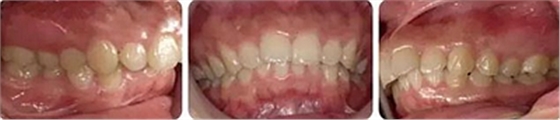

女性,24歲,主訴牙列不齊,面型突。

開唇露齒,閉口時(shí)唇肌緊張,反笑線,突面型。

上下牙列輕度擁擠,牙弓偏尖圓形;前牙深覆合深覆蓋;雙側(cè)磨牙尖牙偏遠(yuǎn)中關(guān)系。

安氏Ⅱ類、骨性Ⅱ類錯(cuò)頜畸形。